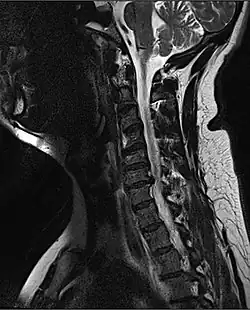

![]() Obrázek magnetické rezonance poranění míchy v krční oblasti | |

K vyšetření a nalezení postižené lokace se užívá nejčastěji rentgenu, pro složitější případy pak také CT a MRI.